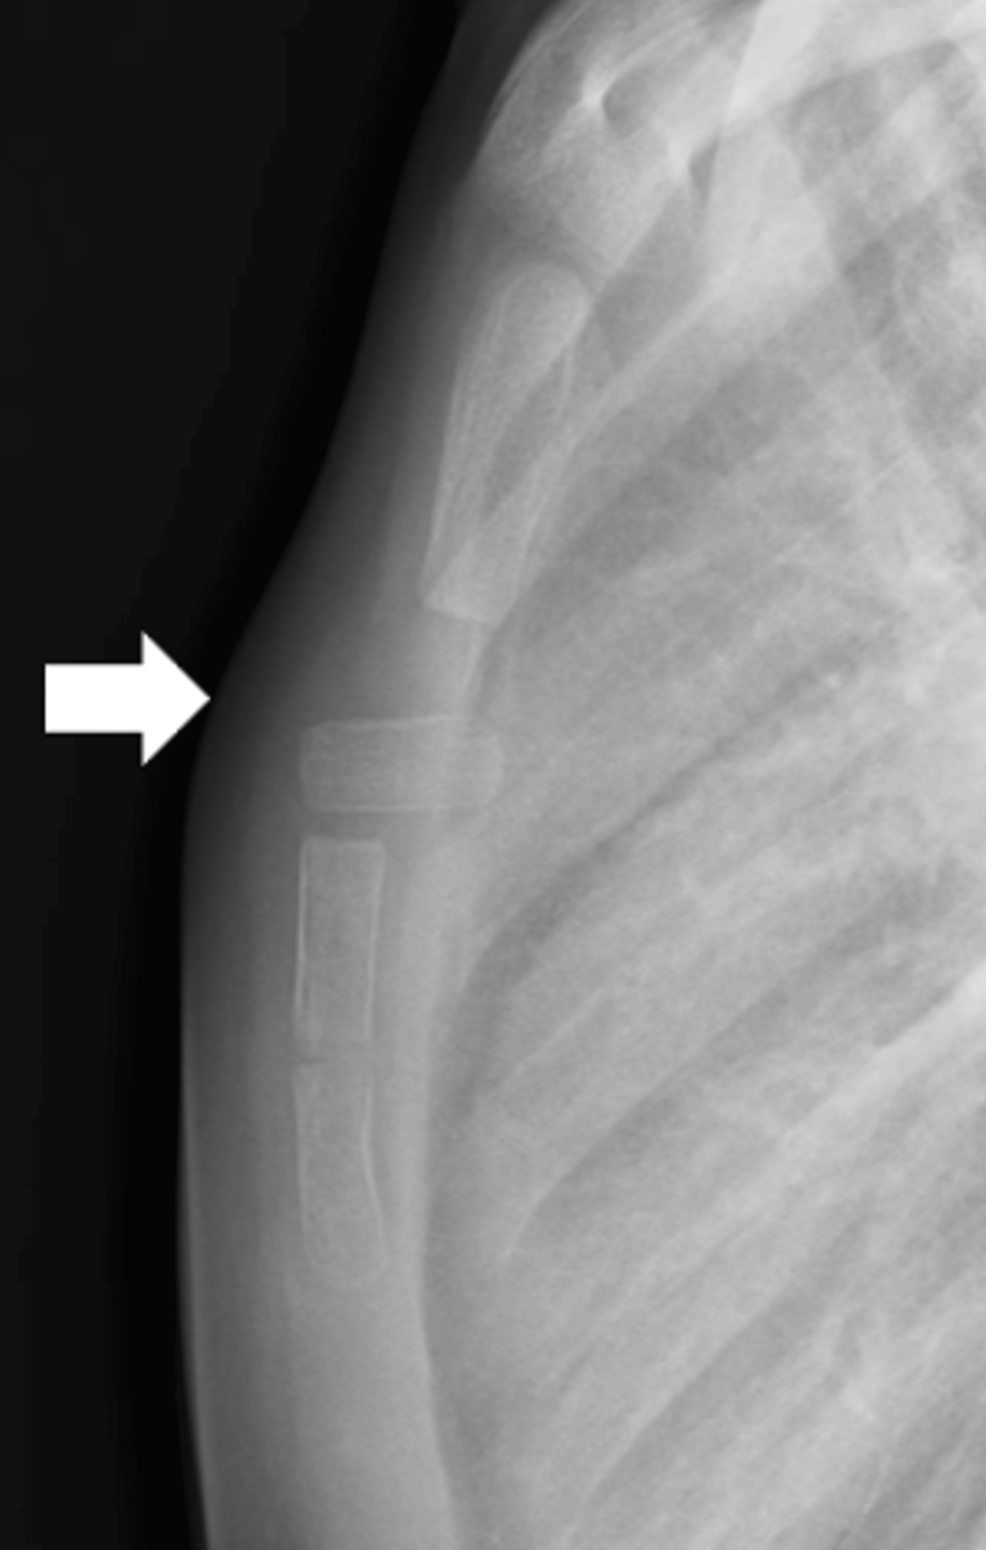

A 7-year-old male presented to the emergency department following a head-on collision. He was a restrained passenger. Initial assessment revealed respiratory distress, bruising across the anterior chest wall, and crepitus upon palpation.Radiographs demonstrated a complete dislocation of the manubrium sterni (the upper portion of the sternum).

* imaging Findings: Chest X-ray revealed displacement of the manubrium. A CT scan confirmed the dislocation and ruled out associated rib fractures or mediastinal injuries.

This case highlights the importance of considering sternal dislocation in patients involved in high-energy trauma, even in the absence of obvious fractures. Chest trauma in children requires a thorough evaluation.

A 5-year-old female presented after a 15-foot fall from a tree. She complained of localized chest pain and difficulty breathing. Physical examination revealed tenderness over the sternum but no visible deformity. Initial chest X-ray was unremarkable.However, due to persistent pain and clinical suspicion, a CT scan was ordered.

* Imaging Findings: The CT scan revealed a subtle sternocostal dislocation at the level of the 3rd and 4th costal cartilages. The initial X-ray had failed to detect the dislocation due to its subtle nature.

This case underscores the limitations of plain radiographs in detecting subtle sternal dislocations and the value of CT scanning in cases of persistent pain or high clinical suspicion. Missed sternal injuries can lead to chronic pain and functional limitations.

Diagnostic Challenges & Imaging Modalities

* Plain Radiographs: Often the initial imaging modality,but can miss subtle dislocations or dislocations obscured by surrounding structures.

* CT Scan: The gold standard for evaluating sternal injuries. Provides detailed bony and soft tissue visualization, allowing for accurate assessment of dislocation and associated injuries. Consider low-dose CT protocols to minimize radiation exposure in children.